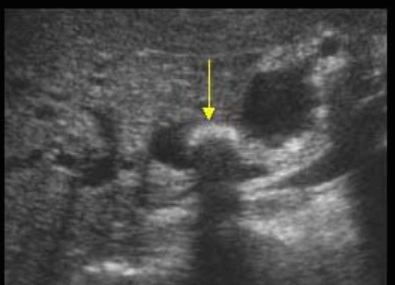

US finding

- 담관 내 무에코의 낭종

- 경계가 분명한 후방음향 증강

- 지방식 검사 후 수축소견이 없다.